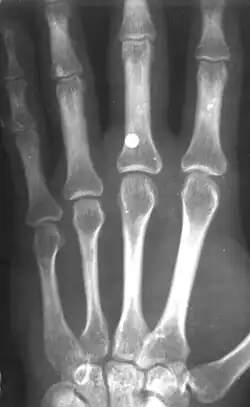

Иноро́дное те́ло (лат. corpus alienum) — с медицинской точки зрения любой чужеродный предмет, попавший внутрь организма. В узком смысле — посторонние предметы различных размеров, попавшие в глаз, ухо, нос, глотку, гортань, в пищевод или трахею (дыхательное горло), заноза.

Инородное тело, даже не повредив окружающие ткани, может стать причиной смерти. Например, в результате удушья, вызванного рефлекторным спазмом голосовых связок или непрофессиональных попыток извлечения инородного тела, приведших к гибели пациента[1], а также в результате контакта со слизистой (например, батарейка может вызвать химический ожог[2]). Дети могут засунуть мелкие предметы, например бусины, в нос или ухо[3]